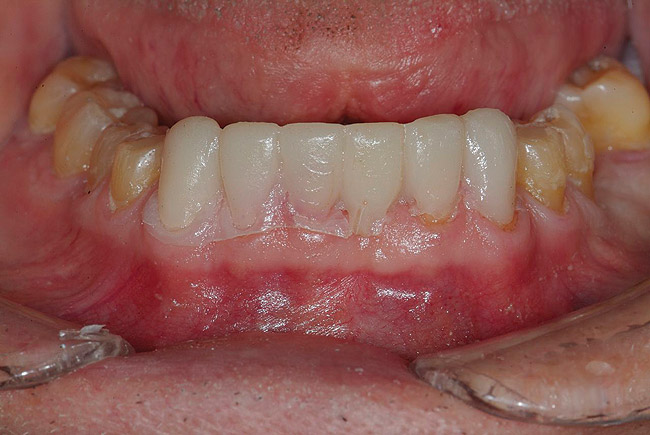

Figure 3  Preoperative view. Note the worn incisal edges and end-on-end occlusal relationship requiring an increase in OVD to restore.

Figure 3